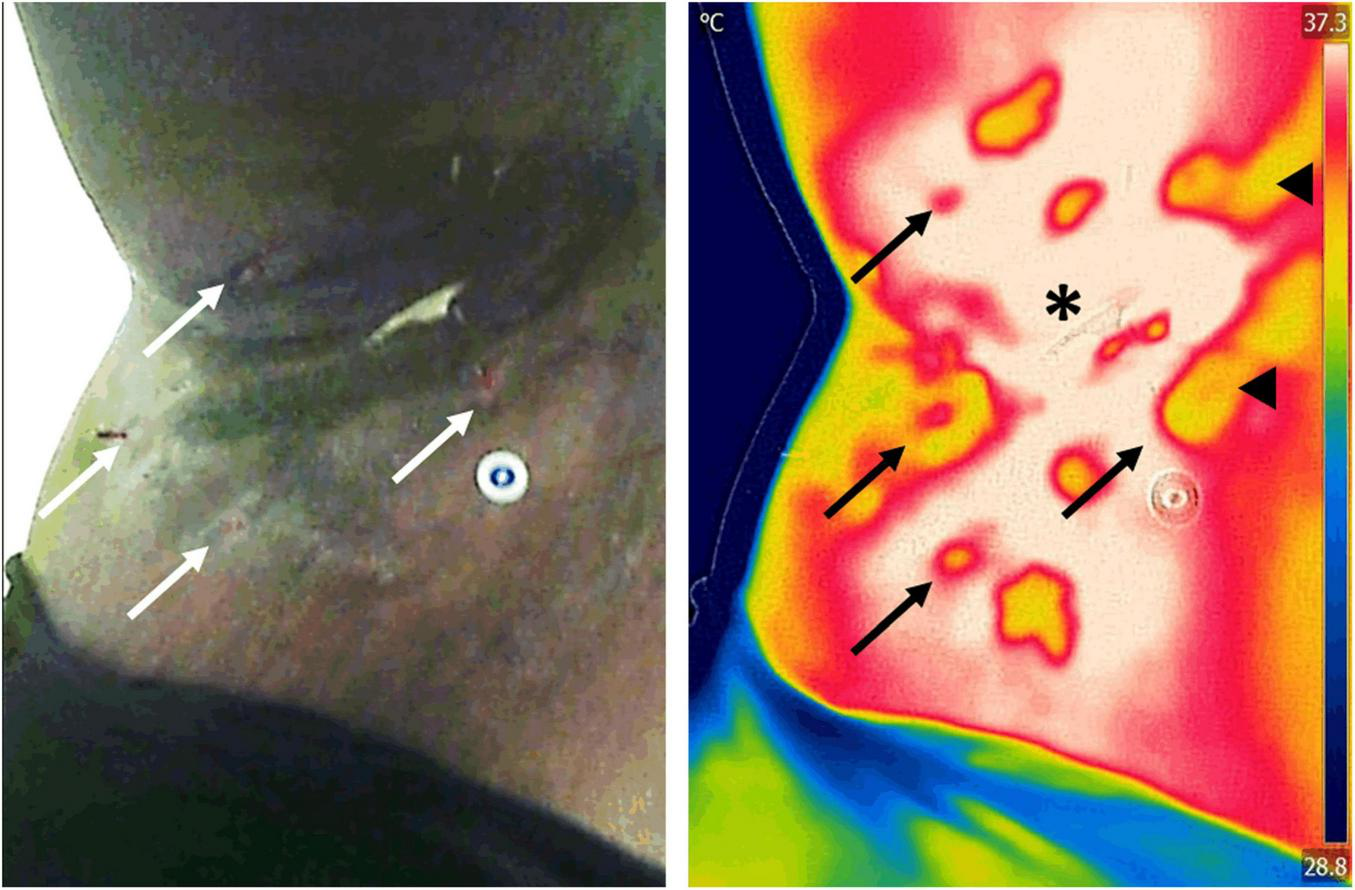

Other Chronic Wound Infections and Inflammations

In the context of skin inflammatory disorders, infrared thermography has proven useful in detecting inflammation and staging the severity of the disease. For example, a positive temperature gradient of 2–4°C was found in the axillae and groins of people suffering from hidradenitis suppurativa, an inflammatory disease of the hair follicles (Zouboulis et al., 2019). Two recent studies demonstrated that in the same disease, when quantified, the positive gradient temperature has a high degree of correlation with several of its clinical staging systems (Ramirez-GarciaLuna J. et al., 2021; Ramirez-GarciaLuna J. L. et al., 2021). Due to the subjective nature of these scoring systems, the authors of these reports recommend using thermography as an objective tool to monitor disease severity and assess response to treatment during clinical trials (Figure 7).

FIGURE 7

Assessment of inflammation in a patient with hidradenitis suppurativa. Infrared thermography was used to assess the severity and area of inflammation in a patient with hidradenitis suppurativa. Assessment of the area of inflammation on regular clinical photographs (left) is challenging in patients with darker skin tones, which leads to subjective patient severity scoring. In contrast, because infrared thermography images (right) are impervious to skin color, hotspots (asterisk) can easily be used to map the extent of inflammatory changes. Previous research has demonstrated that the area of inflammation and its temperature gradient highly correlate with current clinical scores, offering a powerful insight into the underlying condition. Furthermore, thermography is able to identify open wounds (arrows) and tunneling in the dermis (arrowheads) that may not be evident to clinical inspection alone. Images, courtesy of Dr. Sheila C. Wang and JR-G, were acquired using the Skin and Wound mobile app (Swift Medical Inc., Toronto, ON, Canada) paired to a FLIR One Pro mobile camera.